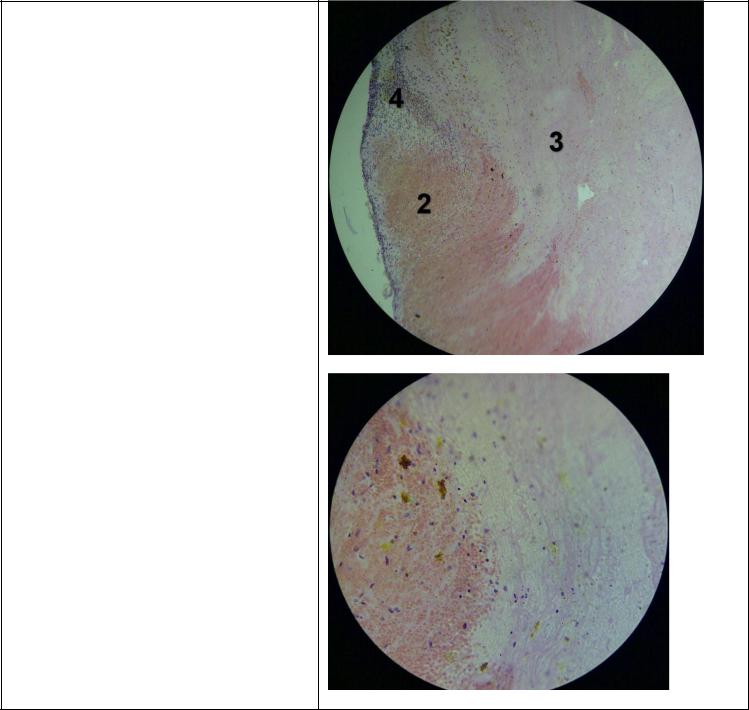

Смешанныйтромб встречается наиболее

часто, имеет слоистое строение, в нем

содержатся элементы крови, которые

характерны как для белого, так и для красного

Тромб занимает почти весь просвет сосуда 1, он состоит из

тромба. Слоистые тромбы образуются чаще в

венах, в полости аневризмы аорты и сердца. В

ТРОМБОЦИТОВ, масс фибрина 3, эритроцитов 2и лейкоцитов 4.

смешанном тромбе различают:

головку (имеет строение белого тромба) –это наиболее широкая его часть; тело (собственно смешанный тромб);

хвост (имеет строение красного тромба). Головка прикреплена к участку разрушенного эндотелия, что отличает тромб от посмертного свертка крови.